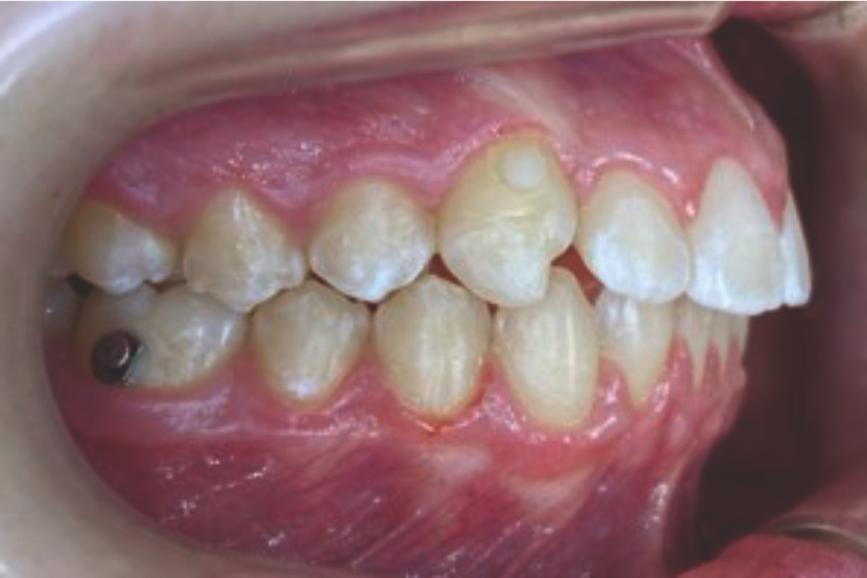

Chief complaint: We present the case of a 12-year-old female patient who came for an orthodontic evaluation, motivated by a family history of treatment. Clinical and radiographic analysis revealed a skeletal Class II malocclusion with molar and canine relationships also in Class II, moderate crowding in both arches, a deviation of the dental midline, and ectopic eruption of tooth 13. No functional issues with breathing or swallowing were observed, and oral health was generally good. A slight mandibular retrusion was noted in the soft tissue profile. A treatment plan was proposed using the Angel Aligner Pro system, aiming to correct dental misalignments and improve facial harmony through a minimally invasive, growth-adapted approach.

- Upper and lower dentoalveolar compression

- Increased overjet and overbite

- Moderate upper and lower crowding

We approached the case by combining upper distalization using the A8 protocol with an asymmetric virtual jump. In this way, we solved the crowding without proinclining the incisors and improved the anteroposterior relationship through the use of elastics. In the lower arch, we carry out a development of the posterior sectors prior to the resolution of the crowding, in order to avoid roundtripping and excessive IPR of the incisors. To achieve an effective extrusion and distalization of 13, we combine the use of direct bonding button on vestibular of 13, with angelButton elastics mesial and distal to the canine. These mechanics help to ensure that the extrusion is real and that the aligner always remains adapted.